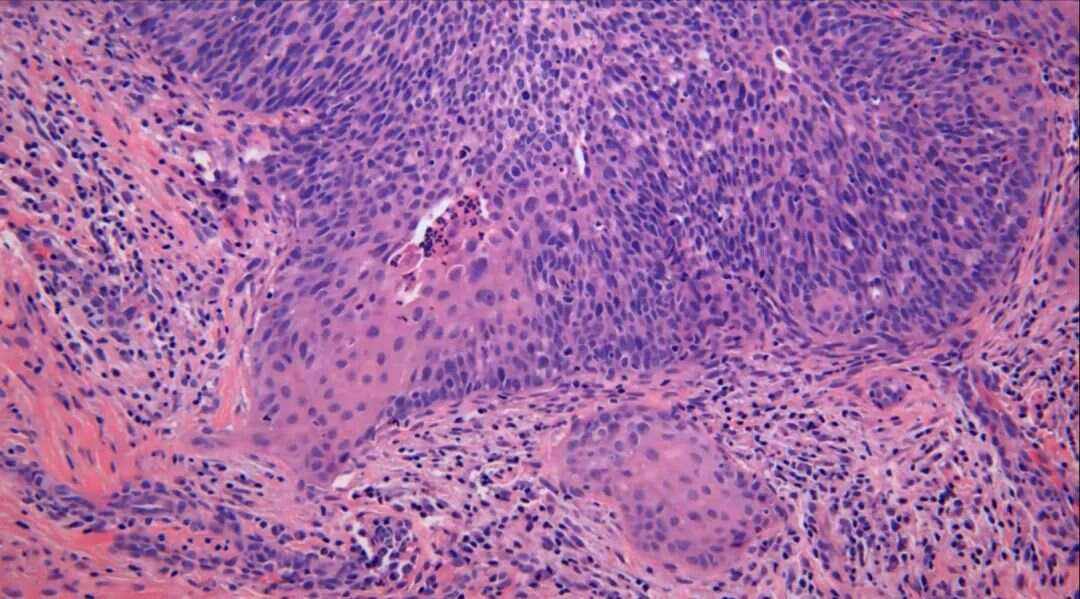

宫颈浸润性鳞状细胞癌的相关信息如下病因高危型人乳头瘤病毒HPV感染是主要病因HPV通过性接触传播,持续感染会导致宫颈细胞异常增生,最终引发癌变除HPV感染外,吸烟免疫功能低下多性伴侣等因素可能增加患病风险症状早期通常无明显症状,部分患者可能出现阴道异常流血如接触性出血白带;宫颈癌浸润性鳞状细胞癌是起源于子宫颈鳞状细胞的恶性肿瘤,癌细胞突破上皮基底膜并侵犯周围组织,属于宫颈癌的主要病理类型症状表现早期通常无明显症状,中晚期可出现阴道不规则出血如性生活后或绝经后出血阴道分泌物异常量增多异味或血性盆腔疼痛下腹或腰骶部泌尿系统症状尿频。

宫颈鳞状细胞,指的就是宫颈的病理组织学中有鳞状细胞成分,属于正常的细胞宫颈鳞状细胞并不就是肿瘤,所以并不可怕只有宫颈鳞状细胞癌,才是需要担心的宫颈鳞癌宫颈鳞癌的形成,多认为与人类的乳头瘤病毒感染以及性活动,还有吸烟等因素有关对于宫颈癌的治疗,需要考虑患者的临床分期,以及细;宫颈鳞状细胞癌是严重的以下是关于宫颈鳞状细胞癌严重性的具体说明疾病性质宫颈鳞状细胞癌是发生于宫颈鳞状上皮的恶性肿瘤,具有恶性肿瘤的侵袭性和转移性,对患者的生命健康构成威胁分期与预后中晚期中晚期的宫颈鳞状细胞癌往往没有手术机会,可能需要放疗化疗以及靶向药物治疗等辅助治疗手段;宫颈鳞状细胞癌属于较为严重的疾病宫颈鳞状细胞癌的发病机制与宫颈鳞状上皮细胞长期受不良因素刺激密切相关这些刺激因素可能导致细胞在自我修复过程中发生异型性增生,最终形成恶性肿瘤其恶性本质体现在病变细胞具有浸润性和扩散性,可突破基底膜向周围组织侵袭,并通过淋巴或血液途径转移至远处器官,增加;垂直深度小于等于3毫米,意味着癌细胞浸润的深度较浅,属于轻度浸润性根据这一特征,医生可以诊断为宫颈癌IA1期IA1期的宫颈癌预后通常较好,患者接受根治性手术治疗后,治愈的可能性较大具体来说,当癌细胞垂直浸润深度不超过3毫米时,这通常被认为是宫颈早期浸润性鳞状细胞癌的一种表现这种情况。